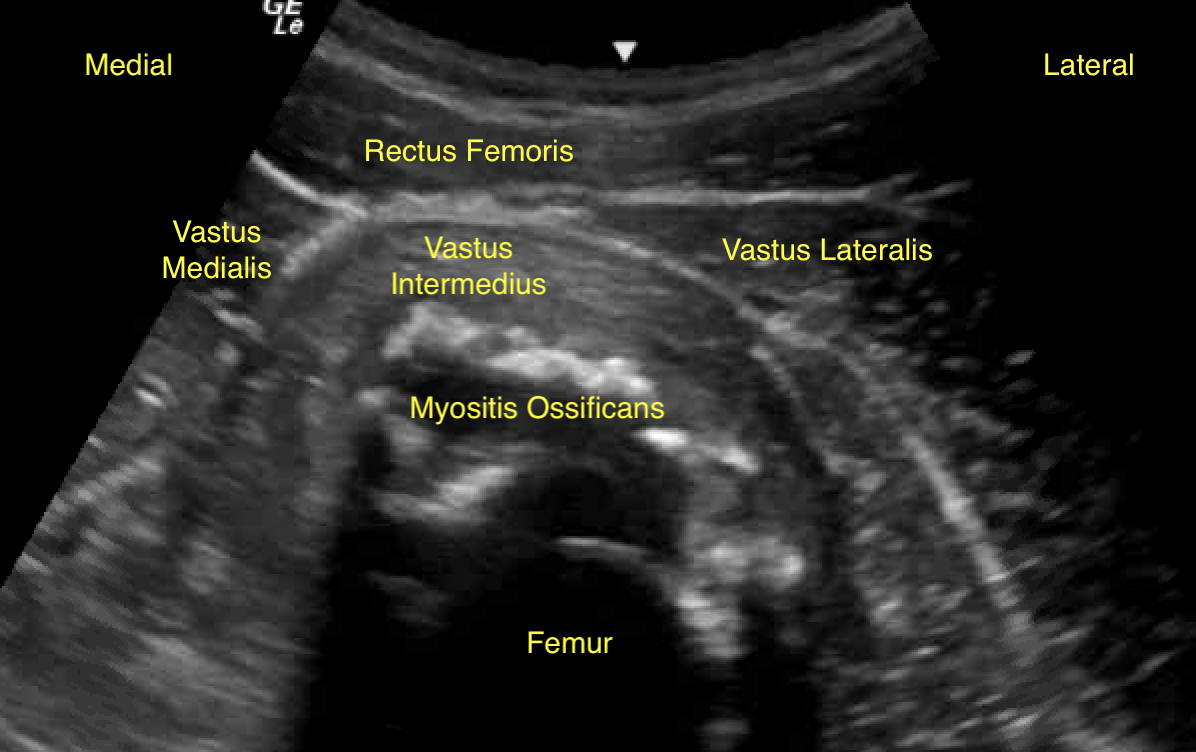

Labeled short axis view of the right quadriceps muscles with myositis ossificans four weeks after initial injury and two weeks after aspiration.

Unlabeled short axis view of the right quadriceps muscles with myositis ossificans four weeks after initial injury and two weeks after aspiration.